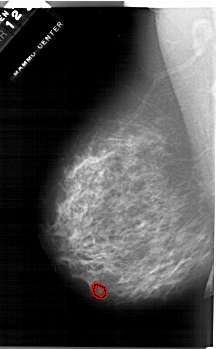

A_1284_1.RIGHT_MLO

RIGHT_MLO LINES 6751 PIXELS_PER_LINE 4081 BITS_PER_PIXEL 12 RESOLUTION 43.5 NON_OVERLAY

FILE: A_1284_1.LEFT_MLO.OVERLAY

TOTAL_ABNORMALITIES 1

ABNORMALITY 1

LESION_TYPE MASS SHAPE OVAL MARGINS OBSCURED

ASSESSMENT 4

SUBTLETY 3

PATHOLOGY BENIGN

TOTAL_OUTLINES 1

BOUNDARY